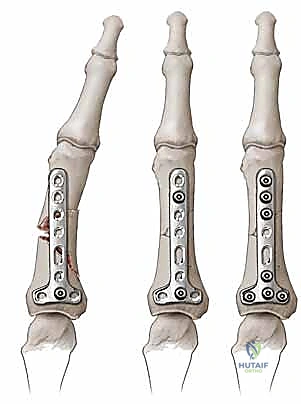

تحذير جراحي هام من الأستاذ الدكتور محمد هطيف:

يجب على الجراح الانتباه بشدة إلى أن زراعة الصفائح المعدنية (Plates) على الجانب الظهري (الخلفي) من الإصبع، حتى لو كانت صفائح دقيقة جداً (Low-profile)، يمكن أن تؤدي إلى اختلال خطير في توازن آلية الباسطة. هذا ينطبق بشكل خاص إذا كانت نهاية الصفيحة عند مستوى المفصل بين السلامي القريب (PIP). على السلامية القريبة، يمكن للصفيحة أن تقصر وتشد الوصلة المركزية للوتر، مما يحد من القدرة على ثني المفصل بالكامل. وعلى السلامية الوسطى، تكون المساحة ضيقة جداً لوضع صفيحة تحت الرباط المثلثي والوتر الطرفي، مما يزيد من خطر احتكاك الوتر وتآكله مع مرور الوقت. لهذا السبب الدقيق، يفضل الدكتور هطيف دائماً وضع الصفائح جانبياً (Mid-axial) أو استخدام طرق تثبيت بديلة (مثل الأسلاك المعدنية أو البراغي المخفية) للحفاظ على الانزلاق السلس للأوتار.

2. الرد المفتوح والتثبيت الداخلي (ORIF - Open Reduction and Internal Fixation):

في الكسور المفتتة أو المعقدة، يقوم الدكتور هطيف بعمل شق جراحي دقيق (غالباً من الجانب لتجنب الأوتار الظهرية) لكشف الكسر وإعادة ترتيب الشظايا العظمية بدقة متناهية، ثم تثبيتها باستخدام:

* البراغي الساحبة (Lag Screws): تُستخدم في الكسور المائلة الطويلة أو الحلزونية لتوفير ضغط قوي بين حواف الكسر.

* الصفائح والبراغي الدقيقة (Mini-plates and Screws): تُستخدم في الكسور العرضية أو المفتتة لتوفير تثبيت صلب وقوي يسمح بحركة الإصبع في اليوم التالي للعملية.